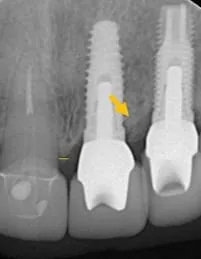

比較最初與植牙後的X片,可見到左邊與自然牙間完整保留原來的骨質(水平線),右邊與植牙間更誘導再生出更多的骨質(箭號),如此牙齦不會萎縮,才能塑型到漂亮。

X光片檢查,門牙已斷裂